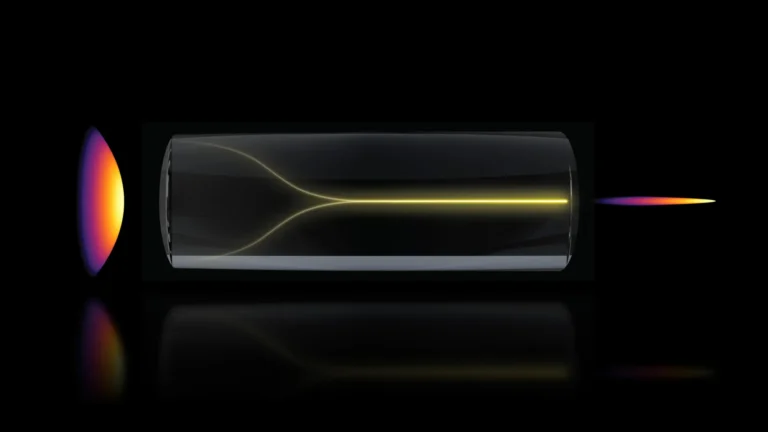

The experimental validation of this CAR-astrocyte therapy involved two distinct groups of mice engineered with genetic mutations known to increase their susceptibility to Alzheimer’s disease. These mice typically begin to develop amyloid-beta plaques by approximately six months of age. In the first group, the CAR-gene-carrying virus was administered before any significant plaque accumulation had occurred. The second group received the same therapeutic intervention after their brains had already become populated with amyloid plaques. Following a three-month observation period, the researchers meticulously evaluated the outcomes.

The results in the younger mice were profoundly encouraging, demonstrating a complete cessation of plaque formation. By the six-month mark, a stage where untreated control mice exhibited brains heavily laden with amyloid plaques, the treated mice showed no detectable evidence of these detrimental deposits. In the older cohort of mice, those that started the study with pre-existing plaque burdens, the CAR-astrocyte therapy proved to be highly effective in reducing the existing amyloid load. The treated mice showed approximately a fifty percent reduction in amyloid plaque levels when compared to a control group that received a virus lacking the CAR gene, underscoring the specific therapeutic action of the engineered astrocytes.